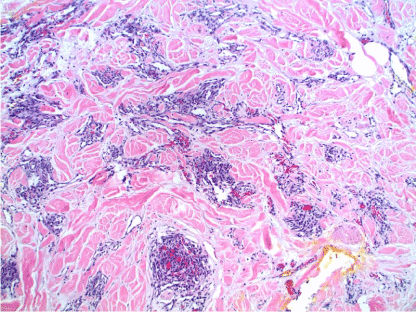

AS of the breast presents clinically as erythematous plaques or nodules, with multifocality or diffuse involvement of the breast not uncommon [13].  Histologically, AS can show heterogenous features, with well-differentiated areas mixed with or directly adjacent to poorly-differentiated components. Extension into the subcutis as well as the breast parenchyma itself is frequently observed, and various combinations of patterns (vasoformative, sievelike, kaposiform, or solid) can be present within a single tumor (Figure 1) [13]. Endothelial cell multilayering is a feature, and intraluminal blood or “blood lakes” may be present [16]. Malignant cells demonstrate prominent nucleoli, brisk mitotic activity, and an infiltrative growth pattern with prominent dissection between dermal collagen bundles (Figures 2-5) [17]. The surrounding normal tissue may show radiation-induced changes including homogenized collagen and mildly atypical dermal fibroblasts [6]. When immunohistochemistry is necessary to establish the origin of the tumor cells, CD31 is the single best marker with high sensitivity and specificity, though caution in interpretation is required as it can also stain macrophages (Figure 6) [13]. Erythroblast transformation specific related gene (ERG), a nuclear stain which is equally as sensitive but not as specific as CD31, is another useful marker that can complement the cytoplasmic/membranous staining of CD31 (Figure 7) [18]. CD34 may be negative in poorly-differentiated areas (Figure 8) [19]. Aberrant cytokeratin expression is an important pitfall, especially in epithelioid AS [13,15].

Figure 1. AS. Biopsy showing poorly-formed vessels infiltrating the subcutis. H&E, 20x.

\